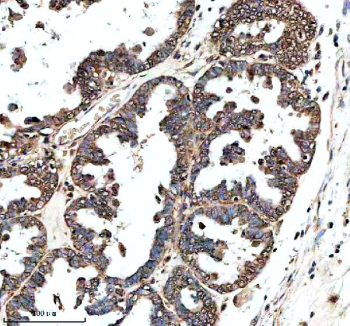

IHC analysis of GHRHR using anti-GHRHR antibody. GHRHR was detected in a paraffin-embedded section of human prostate cancer tissue. Heat mediated antigen retrieval was performed in EDTA buffer (pH 8.0, epitope retrieval solution). The tissue section was blocked with 10% goat serum. The tissue section was then incubated with 2 ug/ml rabbit anti-GHRHR antibody overnight at 4oC. Peroxidase Conjugated Goat Anti-rabbit IgG was used as secondary antibody and incubated for 30 minutes at 37oC. The tissue section was developed using an HRP secondary and DAB substrate.